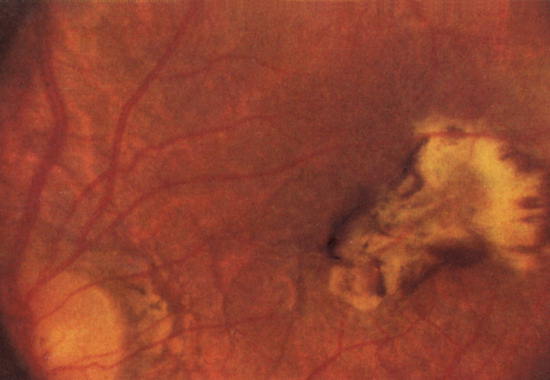

Хориоретинит (исход)

Хориоретинит (исход).